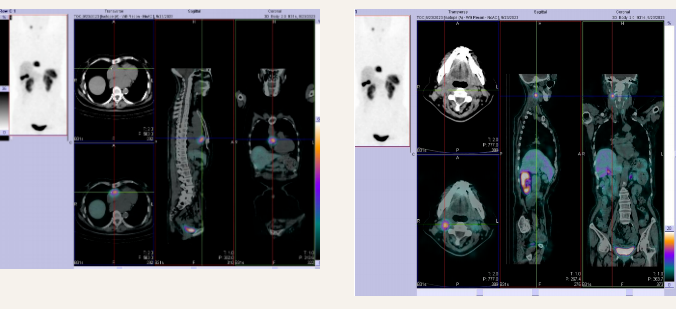

为了明确到底是什么

王阿姨完善了

奥曲肽显像

奥曲肽显像是什么?

这项检查非常关键

他能准确诊断出

神经内分泌肿瘤

还可以用于

神经内分泌肿瘤疗效的判断

与预后评价

终于等到了检查结果

双侧颈动脉体及心脏

为神经内分泌肿瘤

血儿茶酚胺水平

检测结果阳性

奥曲肽显像肾上腺

未见异常